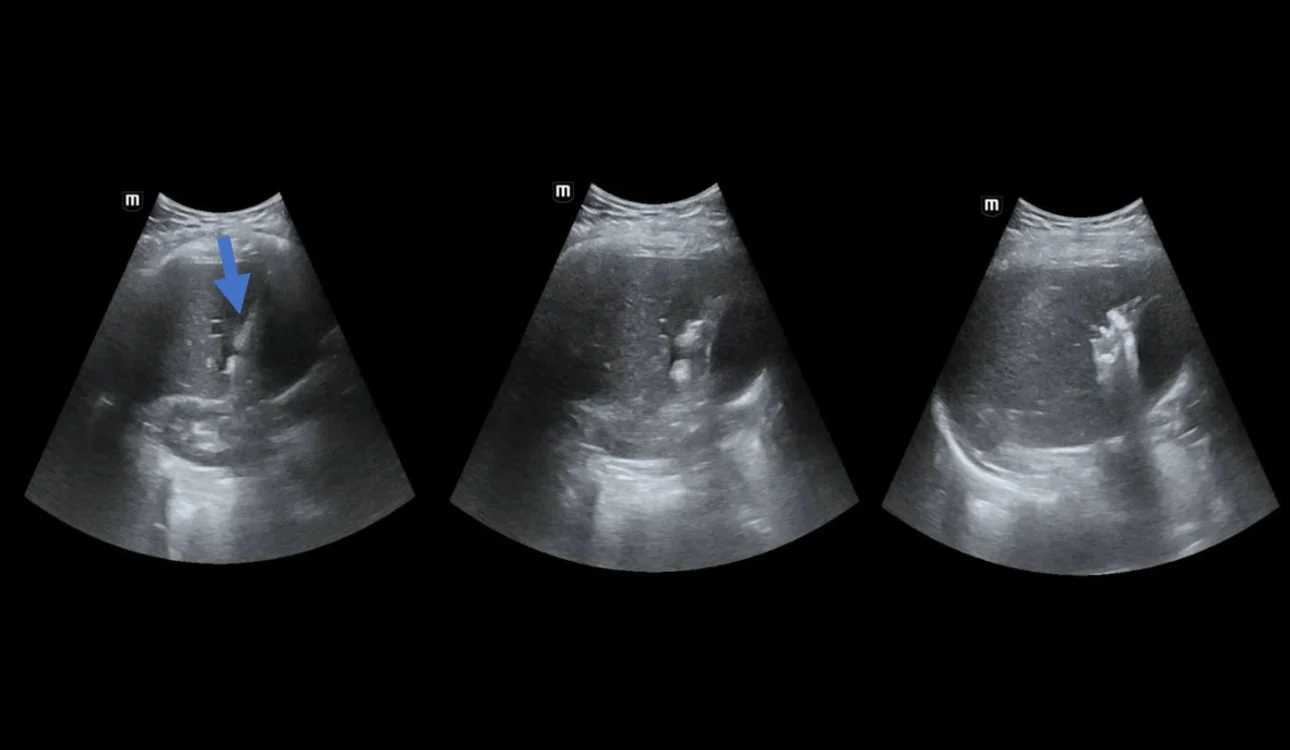

A 57-year-old male patient was treated for rectal cancer. To date, rectal resection and chemotherapy have been performed according to the applicable standard. A follow-up CT scan revealed a lesion in the left liver lobe consistent with a metastasis. Percutaneous radio-frequency thermal ablation (Fig.1) was performed by an experienced operator.

Fig. 1. Percutaneous radio-frequency thermal ablation under ultrasound guidance. Visible electrode (arrow) located in area of the focal lesion. An increasing gas volume was visible during the procedure at the site of thermal ablation in the form of hyperechoic reflections.